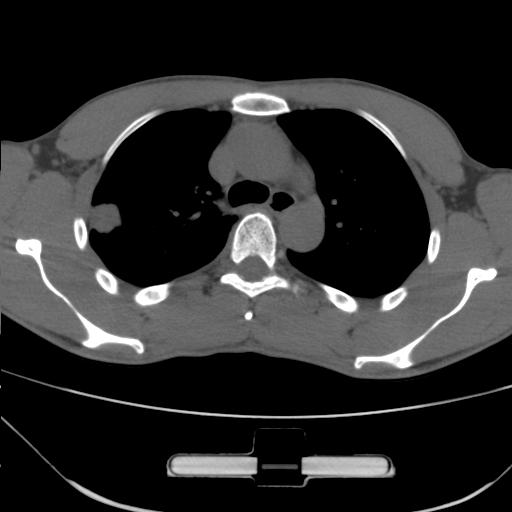

标题: CT25483:肺部病变 请指教

车祸伤者

右肺上叶后段近胸膜下结节样异常密度灶,似见分页及毛刺,考虑右肺上叶周围型肺ca,建议穿刺病理检查

缺乏病史,症状体征,但这个孤立结节具备了几乎所有的恶性征象:分叶,毛刺,空泡征,胸膜凹陷征,血管集束。